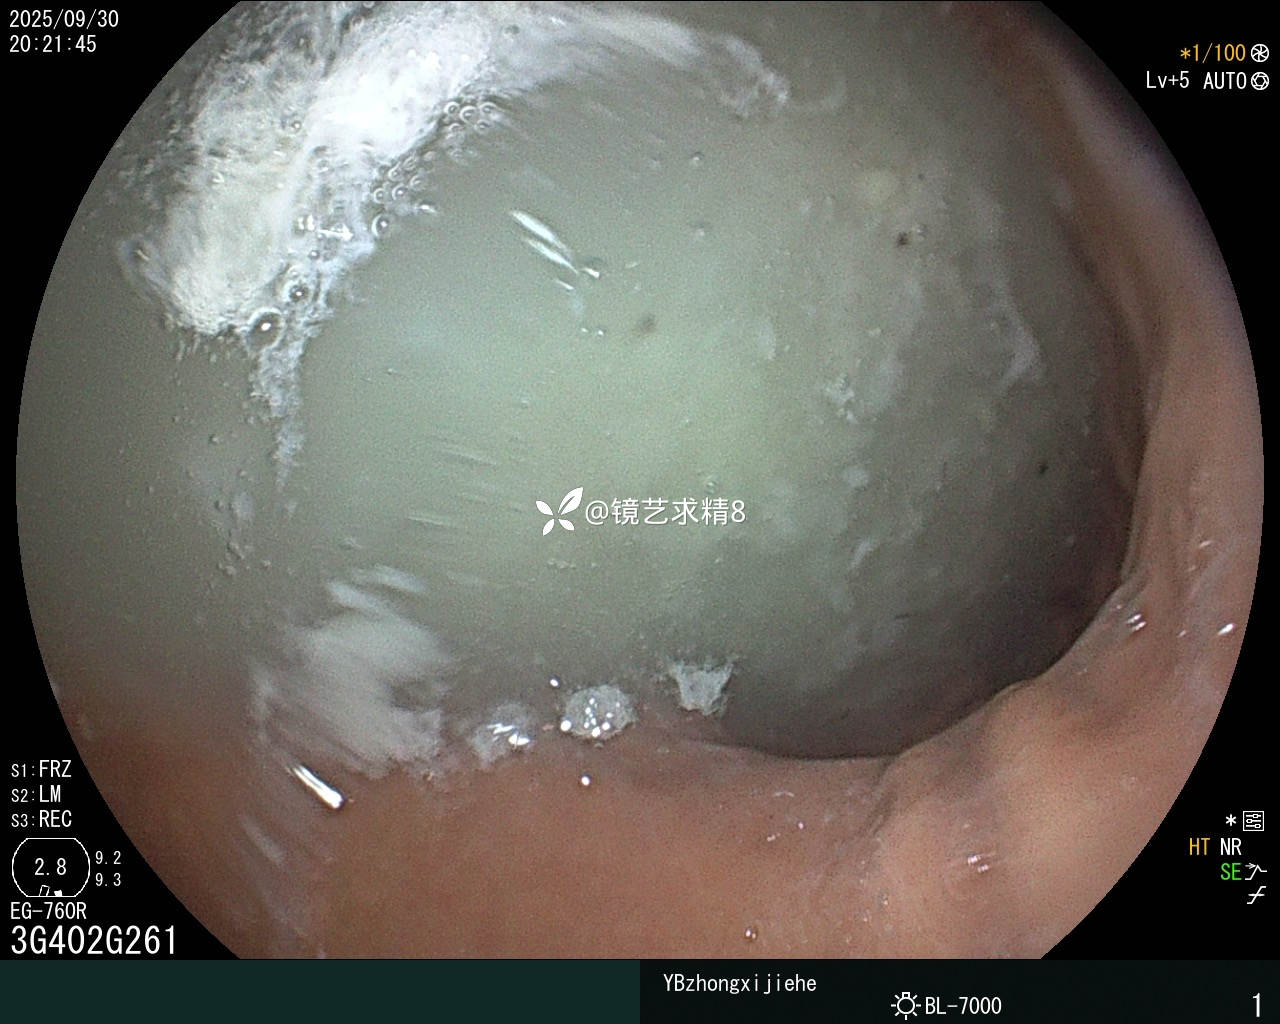

把看不见的肠镜退出来清理镜头上的血渍的过程中,又冒着风险做了一个胃镜,胃镜只过贲门一探究竟,从胃镜图片看,至少可以完全排除胃内出血的可能,全程患者没有恶心、呕吐。

出血范围越来越小,感觉不可能的活检出血和小肠憩室出血需要排除,血液在肠腔倒灌至回盲部、小肠,按照思路内镜先排除活检创面,内镜到达侧向发育型肿瘤部位,看到活检部位渗血,最终把不可能的变成了可能,太罕见了,内镜下给予电凝止血成功,真是第一次遇到,开始觉得不可能的越来越变成了可能。